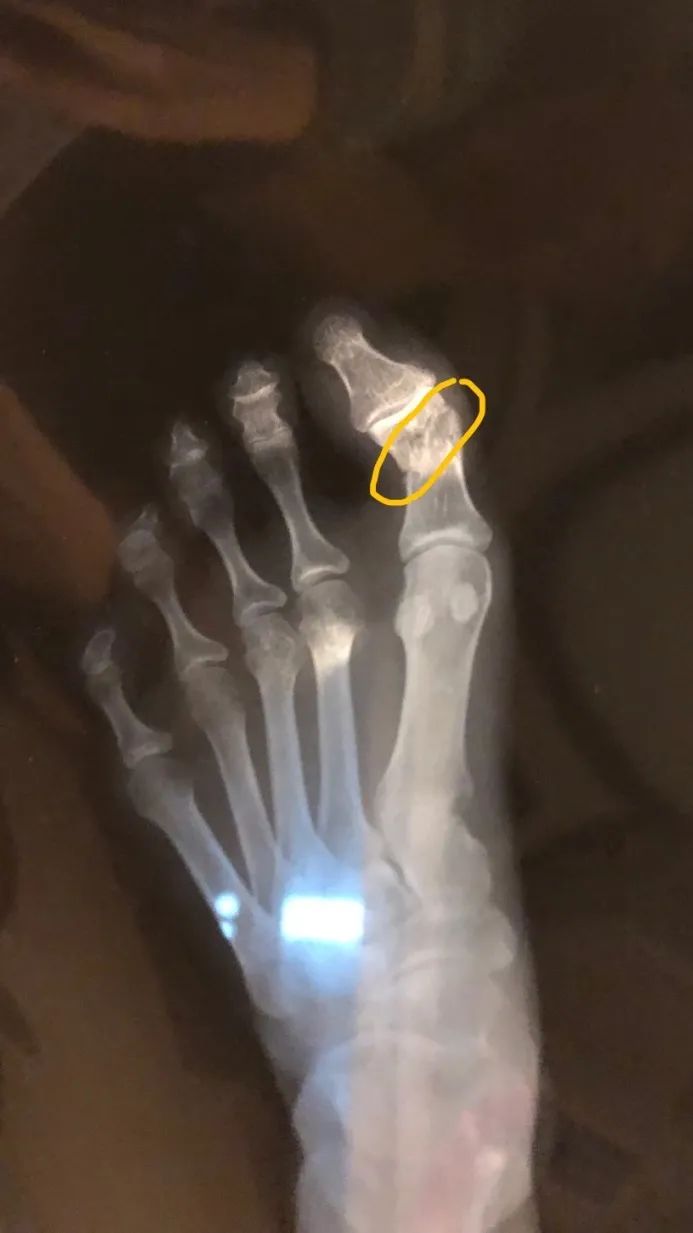

去年我大拇指骨折了。

当时去医院检查的时候,医生怀疑我骨密度不够,否则这个年纪不会那么轻易骨折。

5.容易骨折。